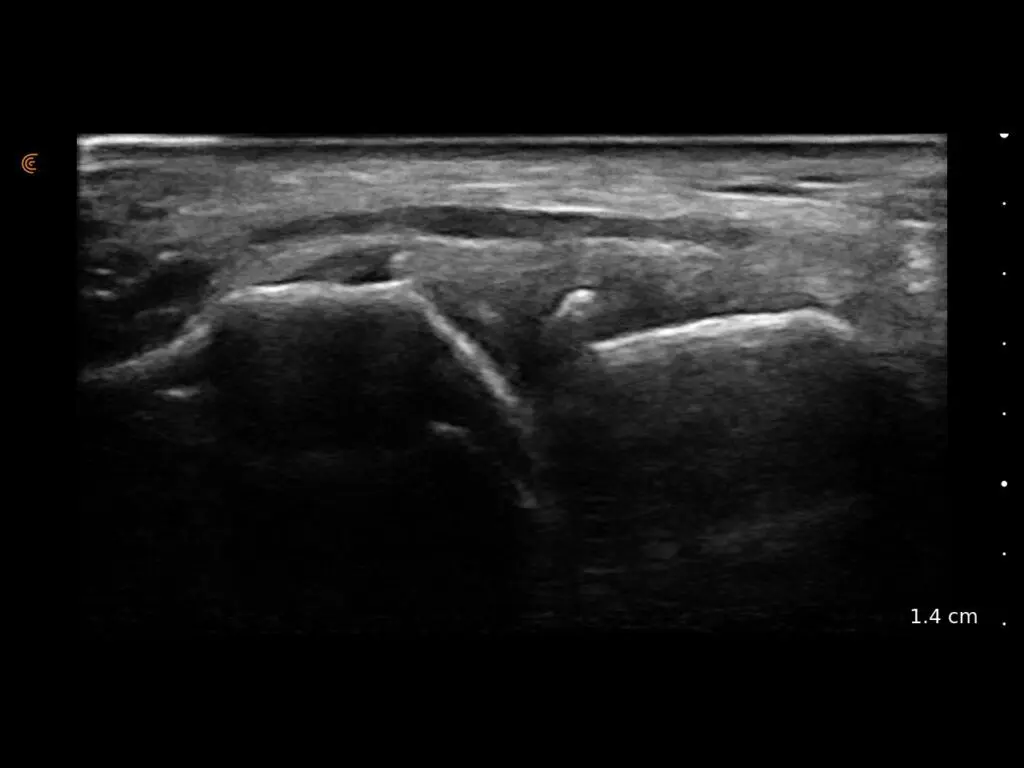

ProbeFix Dynamic is a new device that enables high-quality ultrasound measurements during dynamic exercise by keeping an ultrasound probe in place, allowing for muscle monitoring during intense movement and creating new research possibilities in muscle imaging.